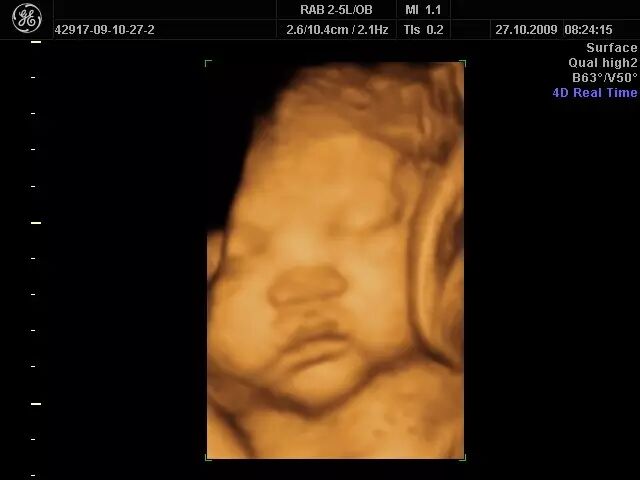

fetus(胎儿)。这是四维彩超下的胎儿。大多数胎儿相册都是利用四维彩超图片制作的。